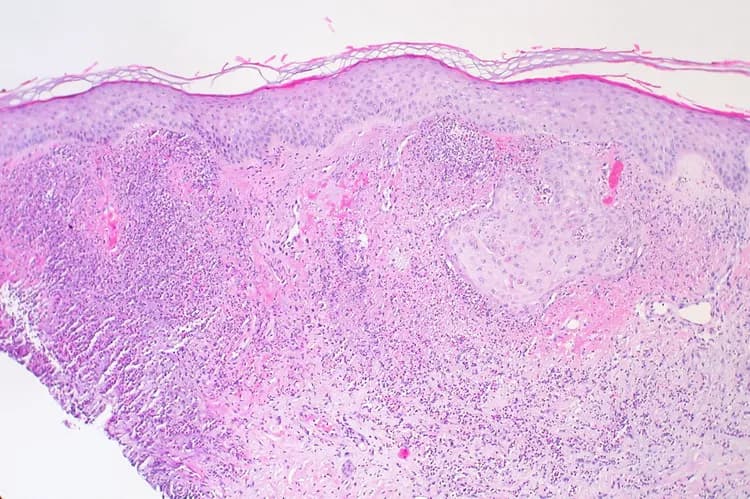

Sweet’s Syndrome is a rare, benign skin disease, with a sudden onset of fever and painful red, inflamed skin lesions, infiltrated by neutrophils (a type of white blood cell). Test your knowledge of this disease by taking our quiz!